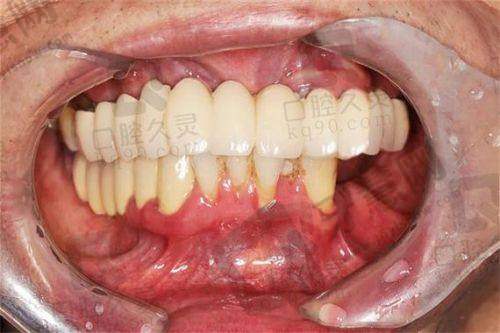

实例2:30岁李女士,前牙缺损选即刻种植,18000元当天告别“豁牙”

李女士因骑车摔倒撞断上前牙,牙根残留无法保留。拜博口腔张医生检查发现牙槽骨条件良好,推荐即刻种植 + 临时牙冠修复。手术采用瑞士士卓曼亲水种植体,拔除残根后即刻植入植体,当天戴上临时牙冠,避免缺牙尴尬。6个月后更换恒久全瓷冠,色泽与邻牙一致,同事均未察觉是种植牙。李女士特别满意:“重要会议前种牙,完全没影响工作形象。”